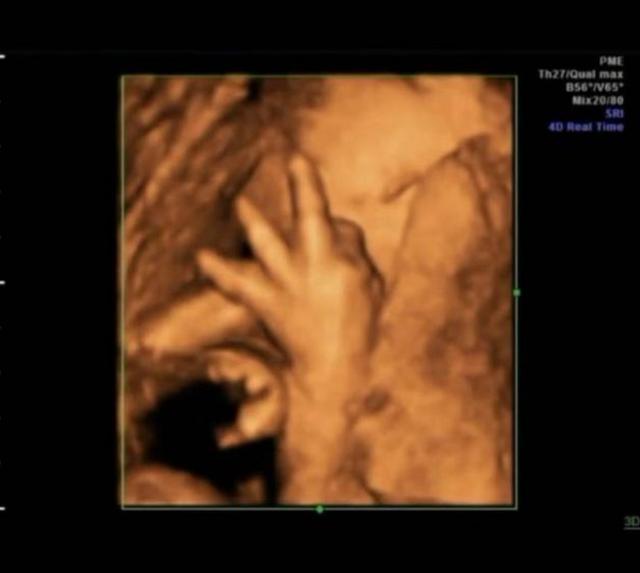

小夏這次去醫院做四維(超音波成像),通過屏幕顯示出來肚子裡的小傢伙正在擺弄著手勢,小夏仔細看了看,好像是數字「4」,她立刻拿出以前做四維的照片給醫生看。

原來小夏每一次做四維她都把胎兒在子宮裡的情況照下來,加上這次正好四次,而每次四維顯示出來的胎兒都在子宮裡擺出不同姿勢和手勢,但是連在一起就非常像小朋友「數數」,因為四次四維圖象連在一起胎兒的手勢正好是數字「1234」。

子宮裡黑乎乎的,胎兒周圍都是羊水,除了臍帶什麼都沒有,胎兒怎麼玩遊戲呢?其實胎兒的玩具就是臍帶,就是因為繞來繞去才有了臍帶繞頸,還有的胎兒會玩自己的手指,所以小夏看見自家寶寶在「數數」可能也是胎兒自娛自樂呢!